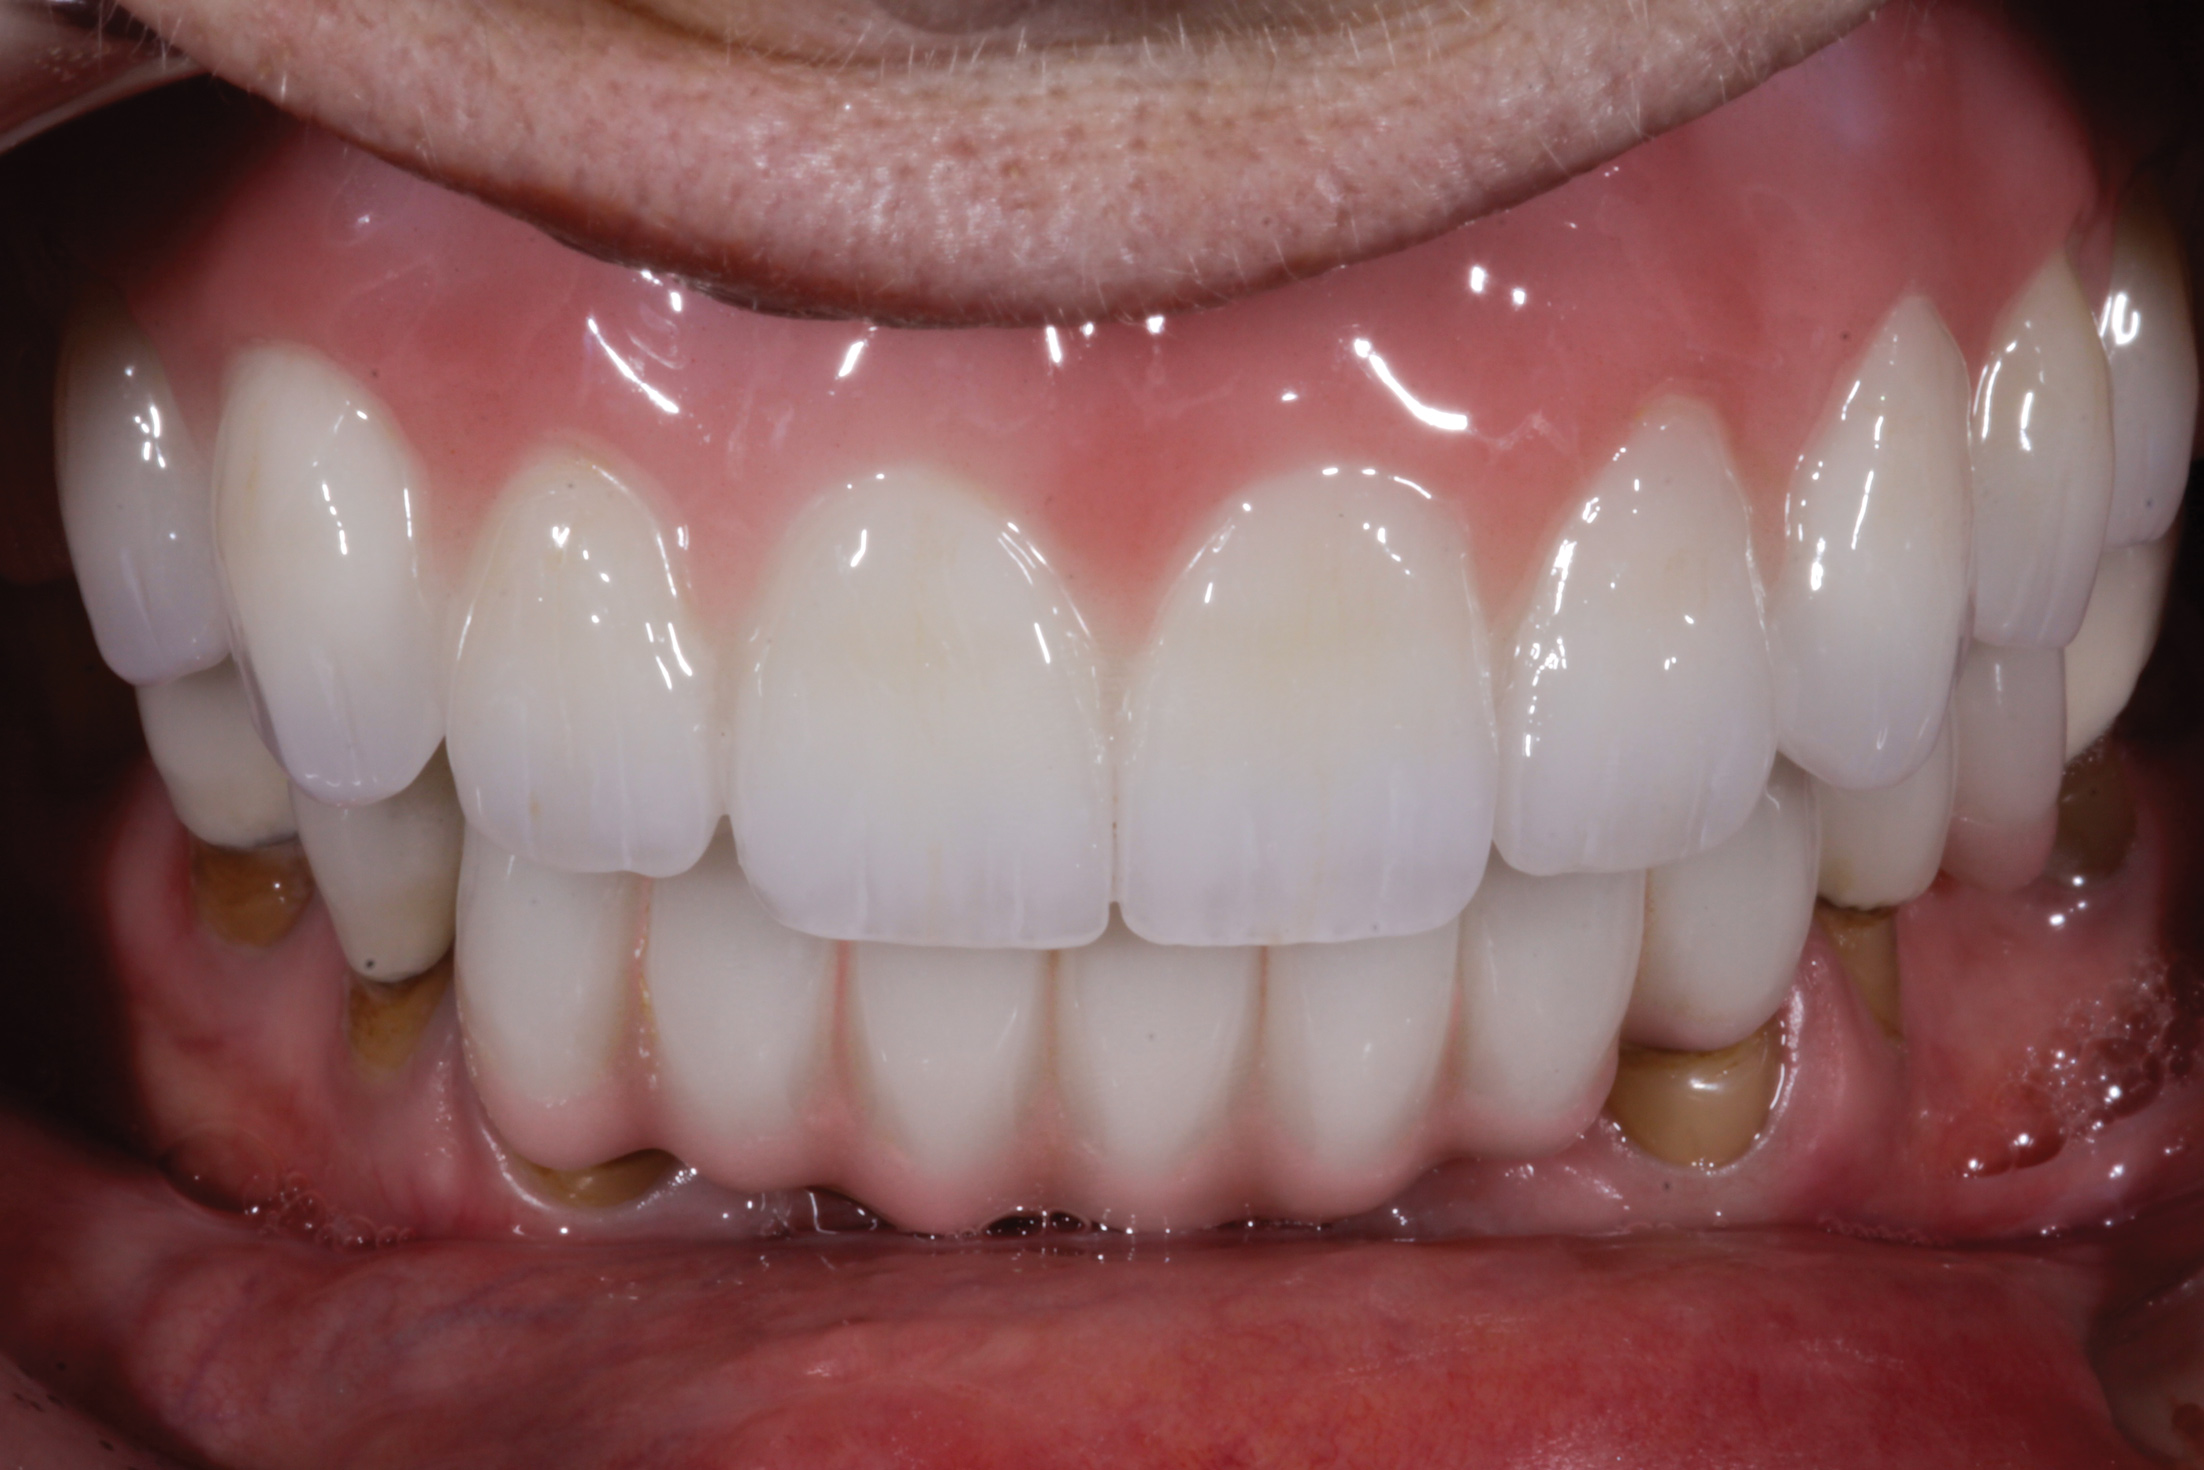

Fig 5. Emergence profile prior to insertion of definitive restoration.

Figure 5

Fig 6. Definitive restoration, demonstrating restored function and esthetics.

Figure 6